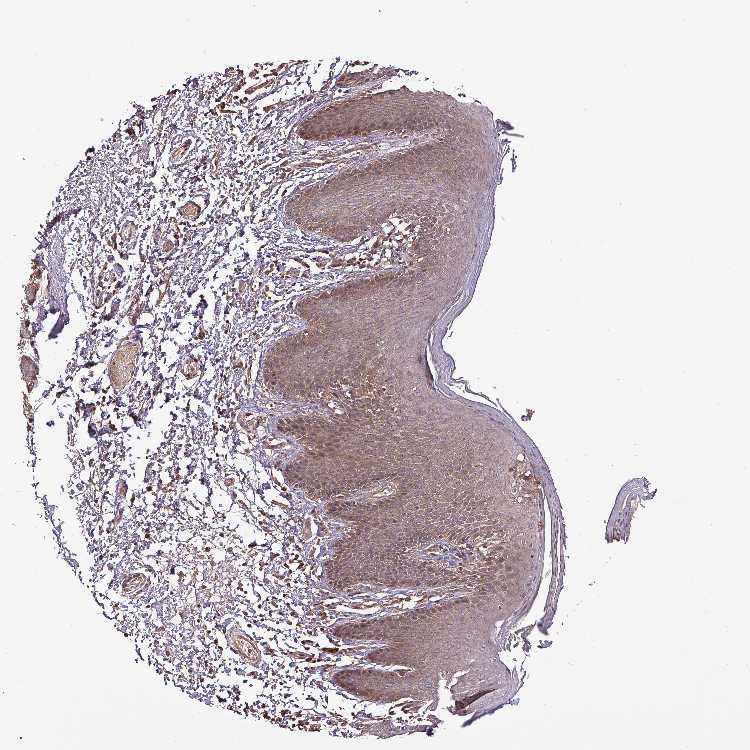

SKIN 1 - Antibody stainingi

Antibody staining in the annotated cell types in the current human tissue is reported as not detected, low, medium, or high, based on conventional immunohistochemistry profiling in selected tissues. This score is based on the combination of the staining intensity and fraction of stained cells.

Each image is clickable and will lead to virtual microscopy that enables deeper exploration of all samples and also displays staining intensity scores, fraction scores and subcellular localization as well as patient and tissue information for each sample.

Antibody HPA051836

Langerhans Not detected

Fibroblasts Low

Keratinocytes Low

Melanocytes Low